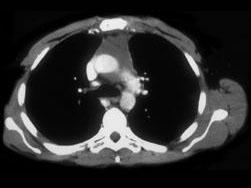

问题 男,64岁,胸部隐痛伴眼睑下垂2个月余,请结合影像学检查图,选出最可能的诊断 ( )

选项 A、纵隔畸胎瘤 B、间皮囊肿 C、胸腺瘤 D、胸内甲状腺肿 E、淋巴瘤

答案 C